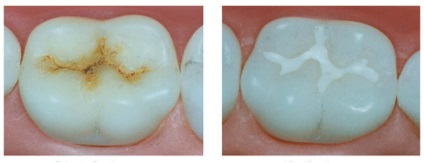

folyamat tömítő

A speciális készítmény tömíti a hornyok a fogat. Miután a gyógyítás, és jön germetiztsiya repedések. Most nem tudok tenni semmit, és csapdába esnek a barázdák és a barázdák a rágás felületén. Ez a technika hatékony a fogszuvasodás megelőzésére.

Anyaga tömítése - Silanti folyadék. A fő jellemzője - jó folyik, amely lehetővé teszi számukra, hogy töltse ki a repedések és gyűrődések a fogat. Kikeményedés után ott nem képződik légbuborékok. Ez magában foglalja a fluor, további védelmet a fog a külső behatásoktól. Silanty átlátszó és színes. Tarka általában azokra a gyermekekre, így látható a folyamat kitöltésével repedések. Átlátszó a fog nem látható, de látható szuvas központ.

Figyelem! A fogorvosok úgy vélik, hogy a fényvisszaverő tömítés jobb megtartani a fogat, mint a tömítőanyagot. De, mivel az átláthatóság, láthatjuk a folyamat fogszuvasodás és időben hozza ellenőrzés alatt. ×

Mérföldkövek barázdazárók: A előállítását és tisztítását a fog bevonóanyag germetizuyuschego, fogakat fényező és helyreállítani a természetes alakját.